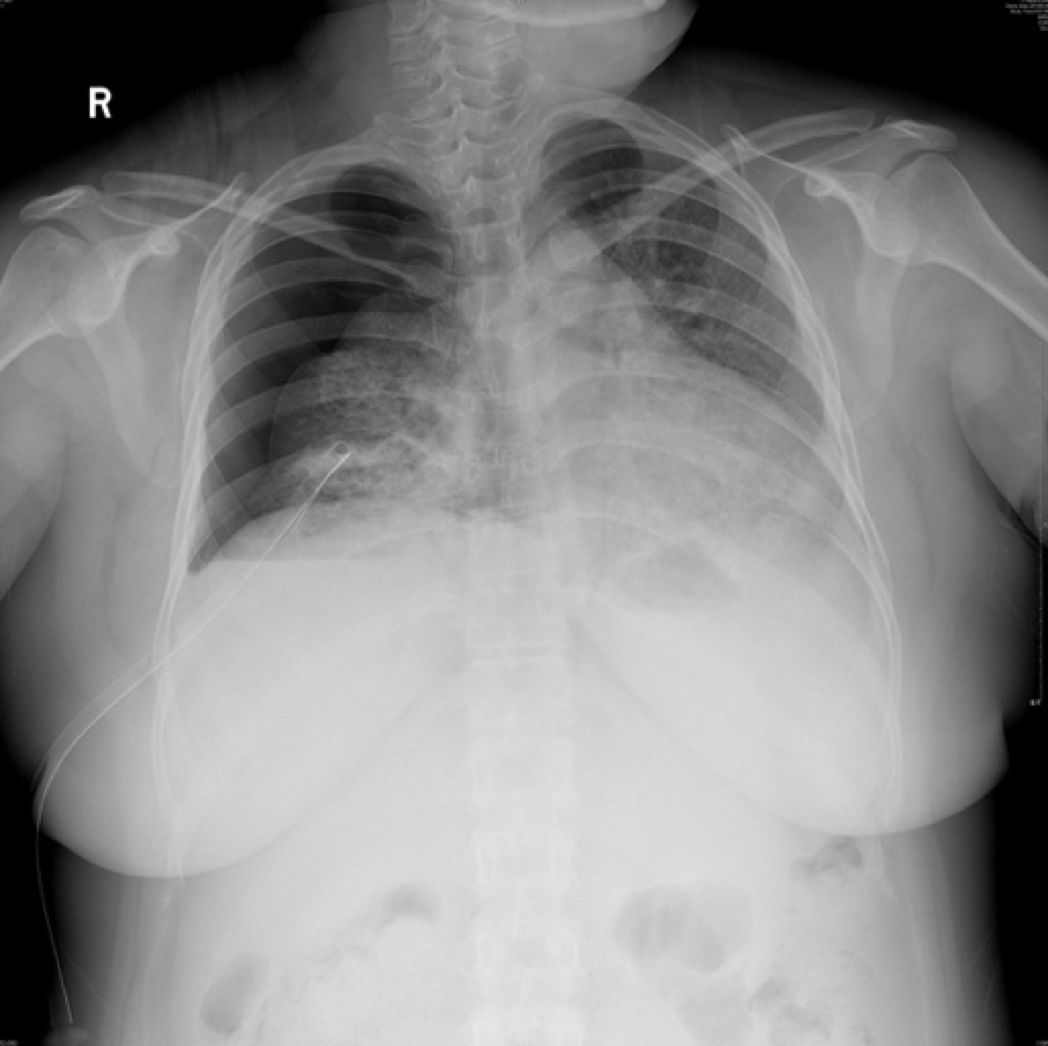

5-16胸片

5-17胸部LDCT

2019-5-21胸片: